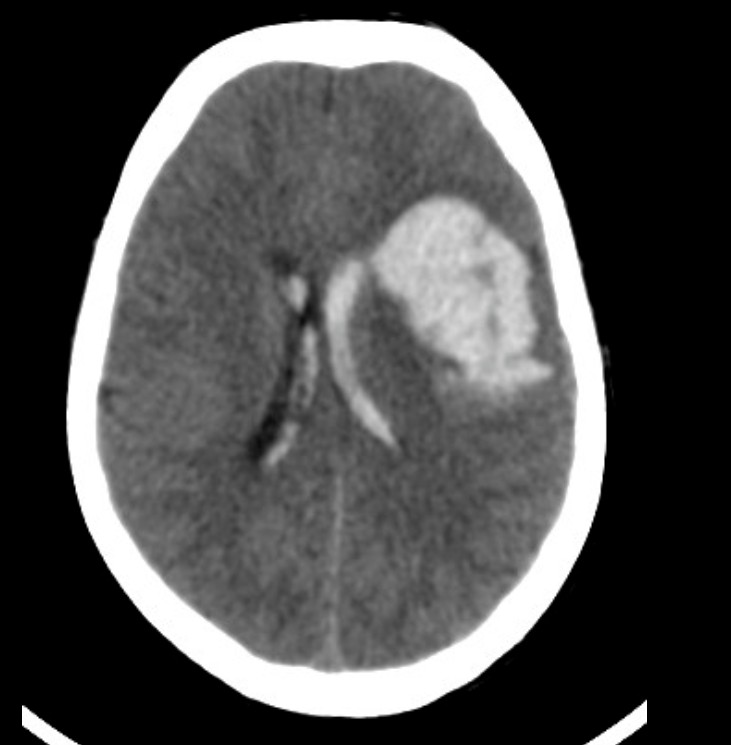

ICH의 brain CT 이미지

뇌내출혈 – 출처 https://radiopaedia.org/